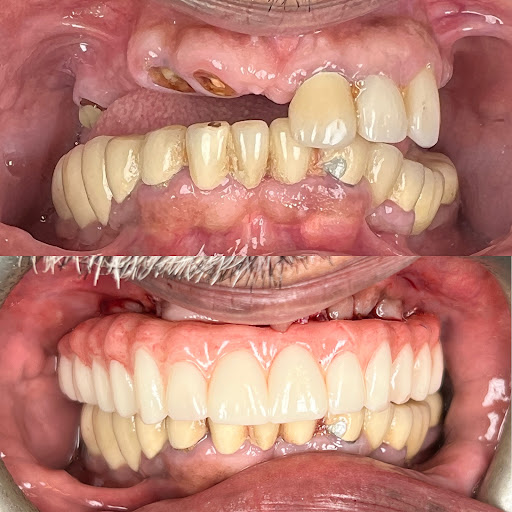

Signature Smiles Family Dentistry

Photos